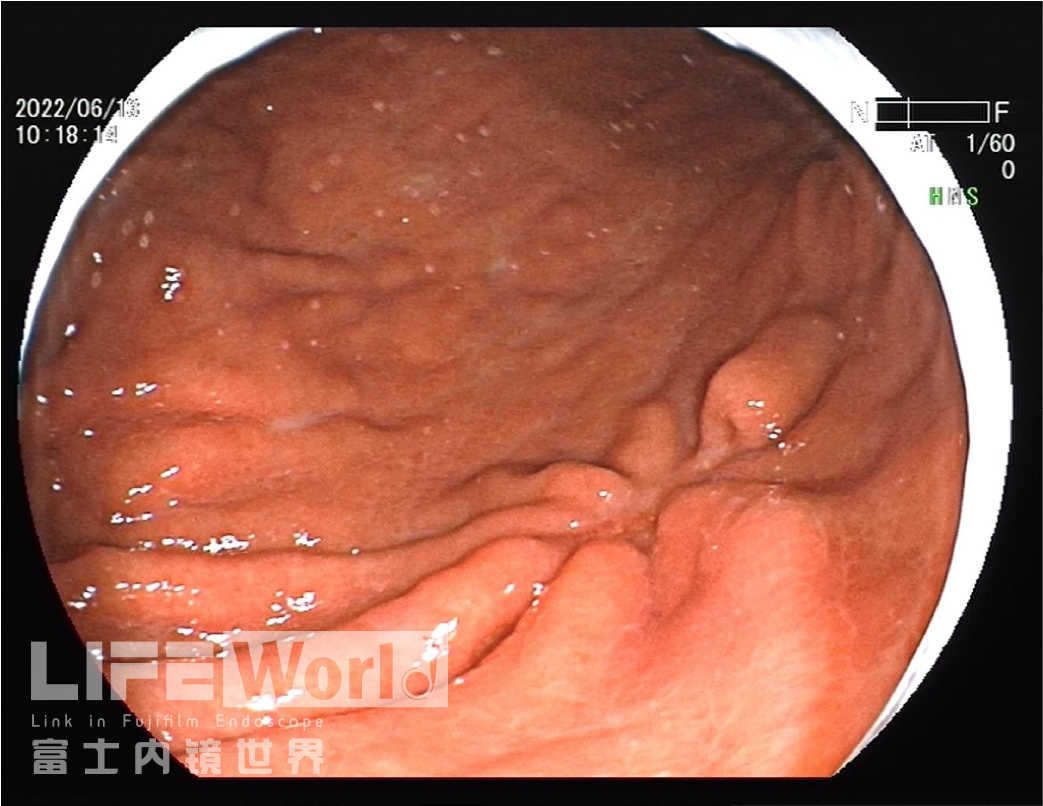

白光观察:胃体下段大弯侧可见一处中央凹陷的病变,色红,范围约1.2×0.6cm,周围黏膜集中、中断。

充气吸气后,可见病变凹陷处延展性欠佳,周围皱襞集中、中断。